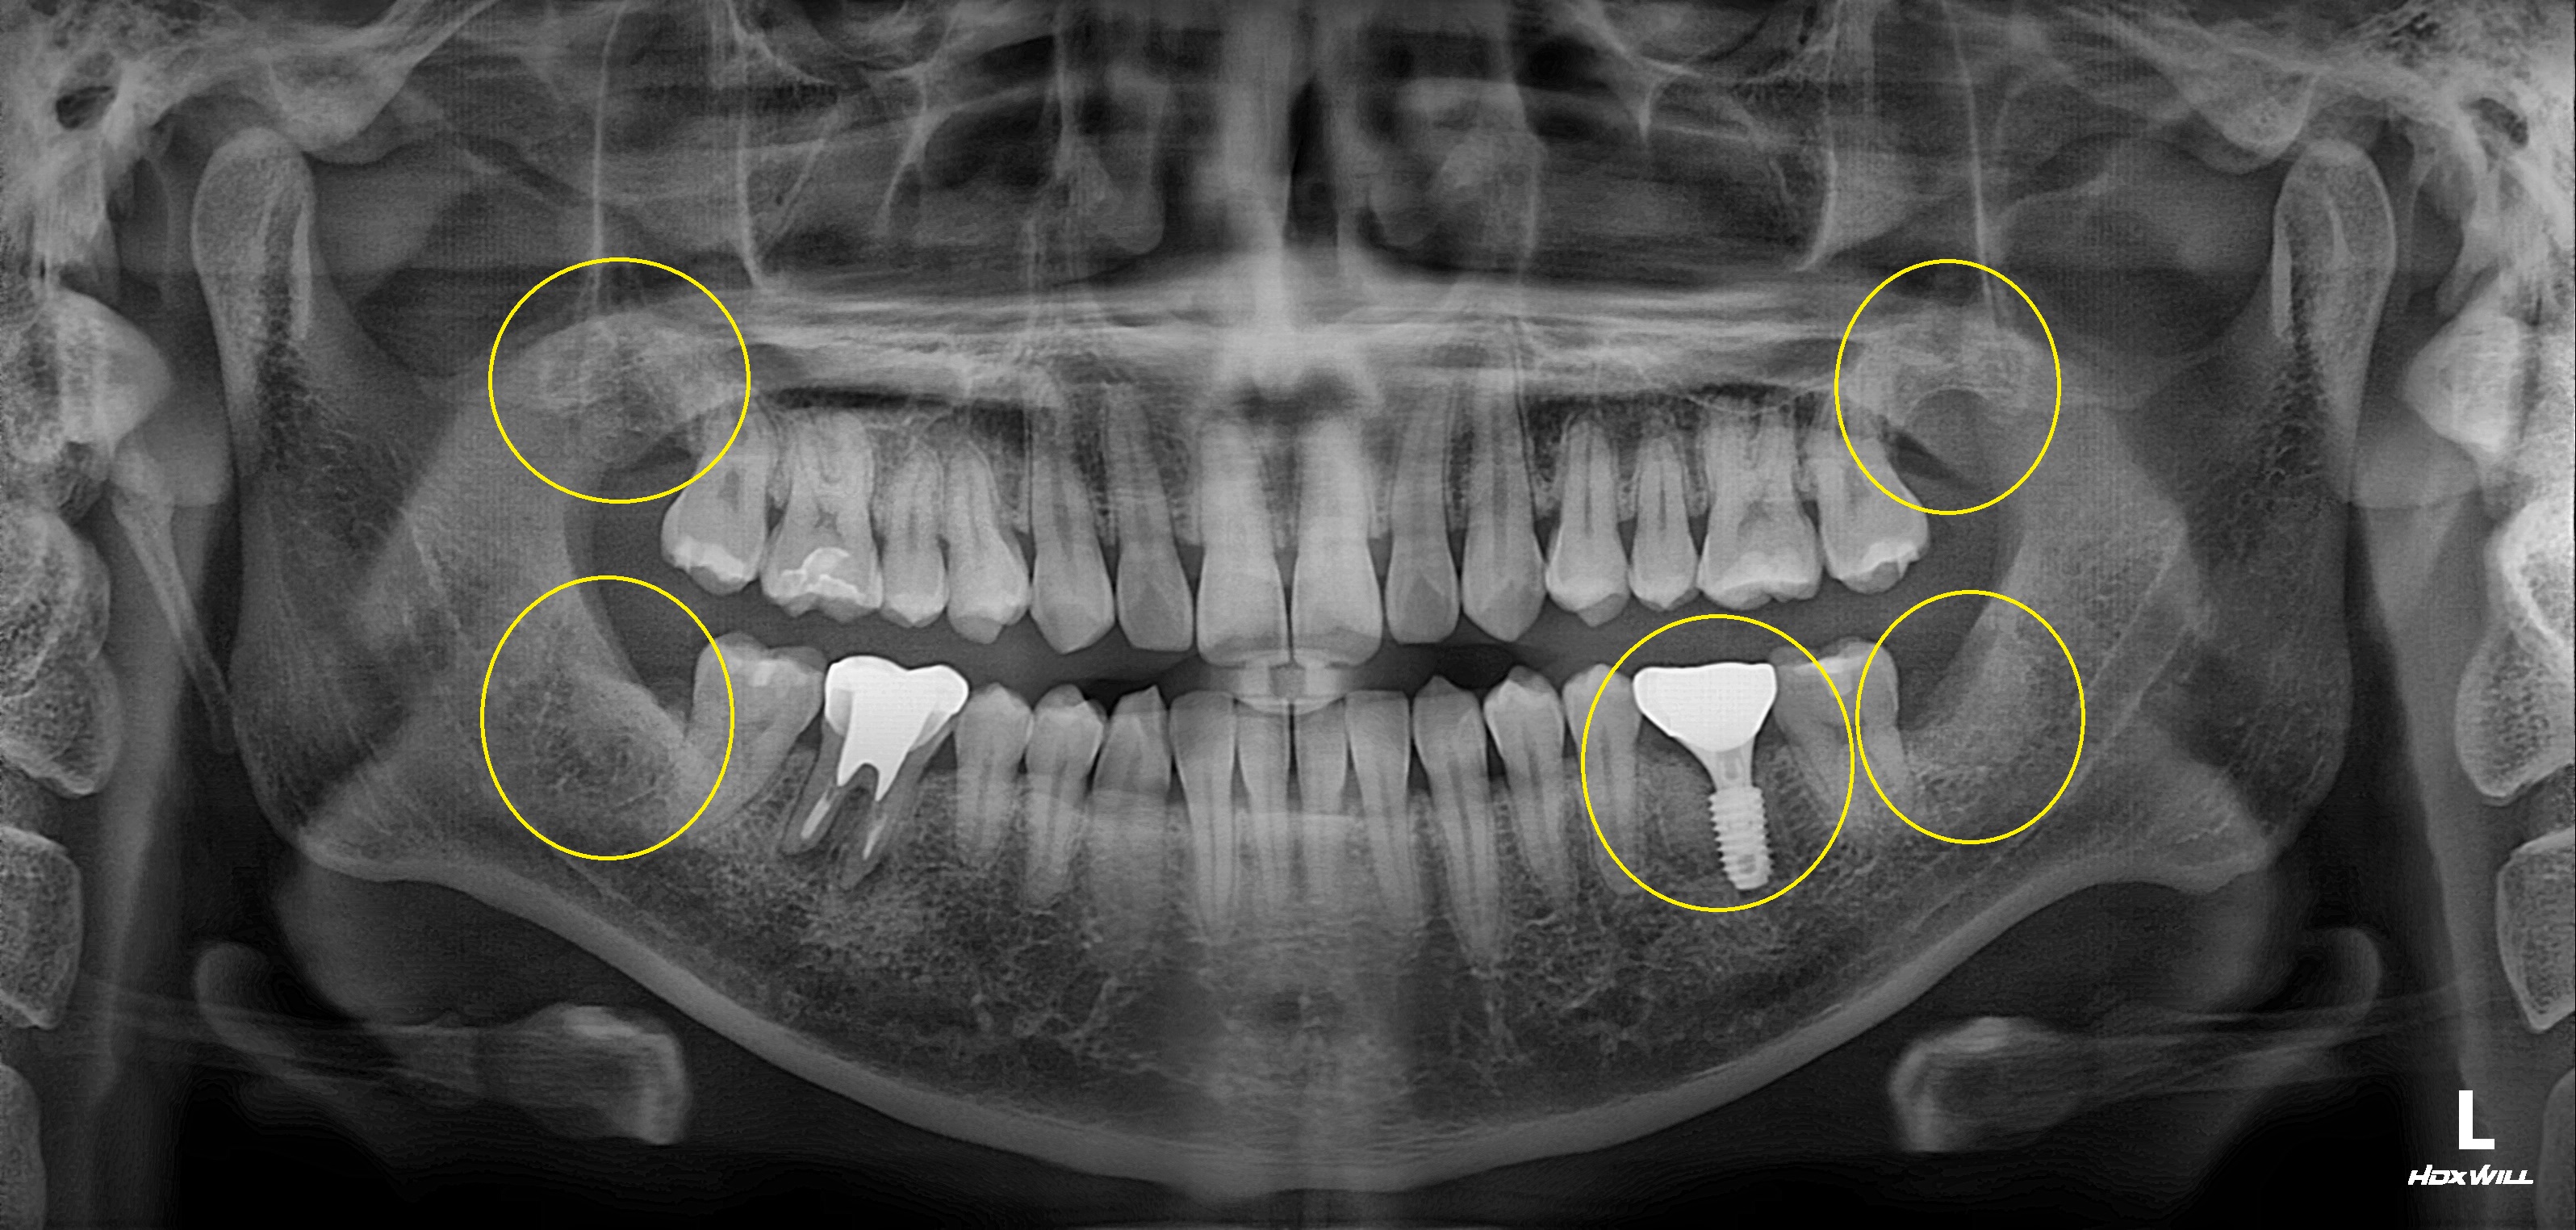

완전매복치사랑니 발치 + 구치부 임플란트 사례

전후사진